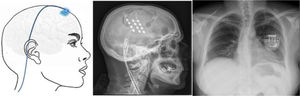

Estimulación cortical motora. Tras localizar el área del dolor facial mediante RM, se realiza una craneotomía guiada por neuronavegador bajo anestesia y se localiza el área de la mano mediante potenciales evocados somatosensoriales intraoperatorios. Los electrodos, generalmente cuatro en una placa, se pueden fijar a nivel epidural o subdural y se conectan a un generador subclavicular mediante tunelización subcutánea del cableado (fig. 8). La eficacia se sustenta en pequeñas series de pacientes que, incluyendo un total de unos 50 pacientes con seguimiento inferior a 40meses, informan una reducción del 50% del dolor en el 45-75% de los pacientes. Las complicaciones observadas son infección, hematoma epidural, convulsiones y efectos adversos cognitivos79.

Figura 8.Esquema y radiografía de cráneo de perfil que muestran la ubicación de la placa de electrodos de estimulación en el córtex motor y el generador subclavicular en un dispositivo de estimulación del córtex motor en una paciente con neuralgia del trigémino refractaria a tratamientos farmacológicos, termocoagulación del ganglio de Gasser (TMCG), compresión percutánea con balón (Mullan) y descompresión microvascular (DCMV) (Hospital de la Santa Creu i Sant Pau).

Estimulación talámica. La estimulación cerebral profunda en la NT es excepcional y se ha realizado en casos secundarios a EM y postherpética, o en dolor facial por desaferentización. En otras ocasiones se habla de NT intratable, sin más. El target habitual es el núcleo ventroposteromedial del tálamo (fig. 9) o la sustancia gris periventricular/periacueductal, o ambos. Consigue una reducción del dolor en el 37-75% en 15 casos comunicados con un seguimiento inferior a 30 meses80.

Figura 9.Esquema, radiografía de cráneo en perfil y tomografía axial computarizada craneal que muestran el trayecto, a través de trepanación, del electrodo de estimulación hasta su inserción en el tálamo en una paciente con neuralgia del trigémino refractaria secundaria a esclerosis múltiple (Hospital de la Santa Creu i Sant Pau).